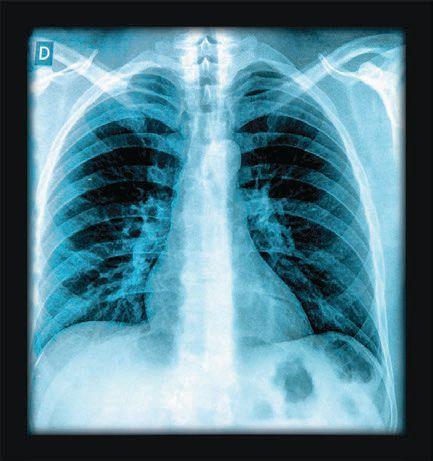

Lung Cancer Screening

In Florida, a yearly average of 11,943 residents are diagnosed with lung cancer, the American Lung Association states in a recent press release. Lung cancer screening is a lifesaving tool, because once symptoms appear, it may mean the cancer has spread and will be more difficult to treat.

“The toll lung cancer takes on our families, friends, and neighbors in Florida and across the nation is truly devastating,” Steven Riddle, executive director of the ALA in Florida, says in the release. “With the availability of lung cancer screening, we have the opportunity to find the disease earlier and save lives. However, to make this lifesaving opportunity a reality, we must do more to raise awareness of both lung cancer and screening.”

• A low-dose CT scan is the only tool that reduces the lung cancer mortality rate for those at high risk.

• Screening is not recommended for everyone.

• See savedbythescan.org or ask your doctor to assess your risk.

• Raise awareness. Despite the attention to lung cancer, awareness remains low among those with high risk.

• Screening is covered by most Medicare and most health-care plans.